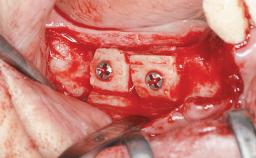

Iliac and Calvarial Bone Blocks for Onlay Grafting of a Severely Resorbed Edentulous Maxilla

A 45-year-old woman with a completely edentulous maxilla was referred to evaluate the possibility of rehabilitation with an implant-supported prosthesis. This patient was healthy and a non-smoker. She had been wearing a maxillary complete denture opposing a natural mandibular dentition since her twenties. This situation had resulted in progressive resorption of the alveolar ridge, repeatedly creating a need for relining the denture. Twenty years later, despite multiple adaptations and the use of “glues” the denture was unstable and causing the patient psychological and functional discomfort.

Bone Augmentation Horizontal|Sinus Floor Elevation|Staged|Vertical

Augmentation Materials Autogenous chips|Autogenous block(s)